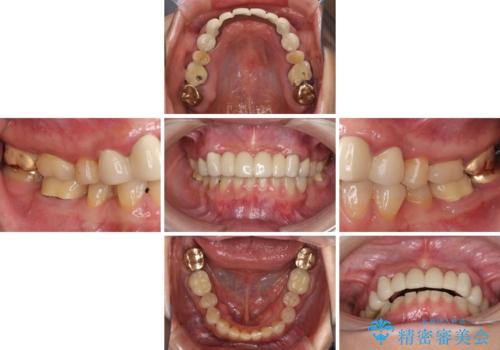

- 全顎的な歯肉からの出血と前歯の形態を気にして来院された患者様です。

診査の結果、上顎奥歯を中心に深い歯周ポケットが認められたため、歯周ポケット除去を目的とした歯周外科処置を行うこととしました。

また、前歯のブリッジへの咬合力の負担が大きく、土台となっている歯が揺れてしまっていたため、インプラント埋入により奥歯への負担を軽減することとしました。

歯周外科処置を行ったことで歯周ポケットはなくなり、毎回のブラッシングの度に嫌な思いをしていた出血は認められなくなりました。

上下前歯の見え方を気にされており、歯だけをみると大変長くなりましたが、笑ったときの口元は自然な外見となり、患者様には大変満足していただきました。